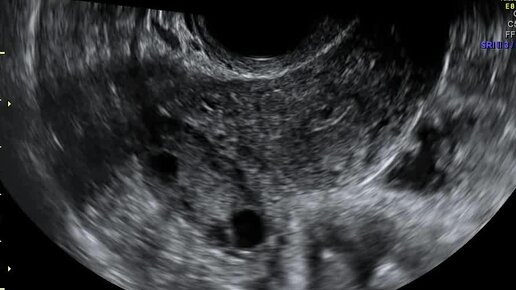

Видео: правый яичник расположен по заднебоковой стенке матки

Ультразвуковые находки от врача УЗД Зорина Я.П.